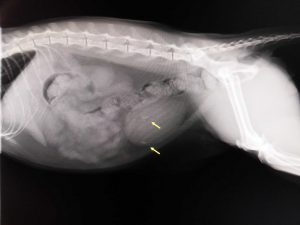

膀胱結石の摘出手術